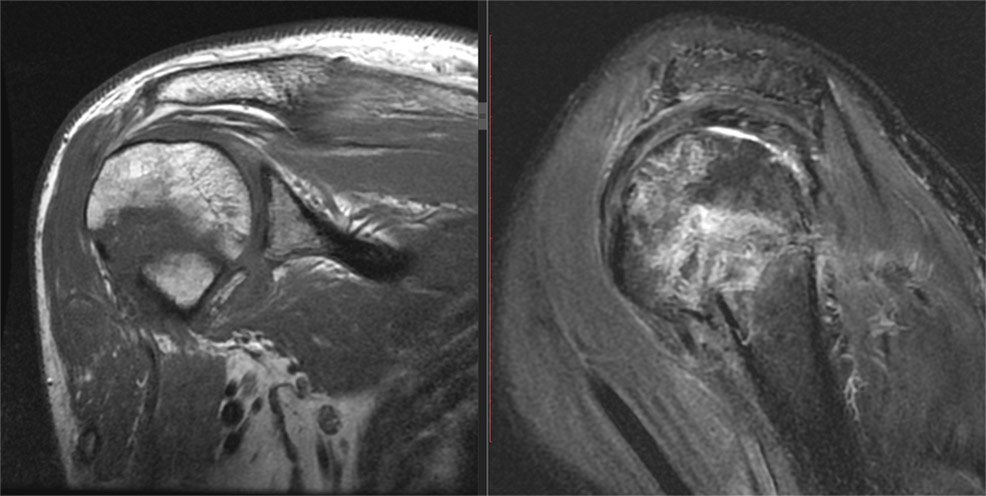

Examinarea prin rezonanță magnetică a umărului

Pacientul ajunge la rezonanța magnetică în urma unui consult clinic efectuat de medicul ortoped sau de altă specialitate, cu o suspiciune de diagnostic clinic (exemplu: “suspect leziune de supraspinos”).

Examinarea prin rezonanță magnetică a umărului este uneori dificil de suportat de pacient, mai ales atunci când acesta este într-o fază dureroasă acută. Poziția în magnet, deși în decubit dorsal (culcat pe spate), necesită ca brațul pacientului să fie rotat spre exterior, ceea ce poate fi dureros. Poziția aceasta este necesară pentru stabilirea unui plan corect al secvențelor rezonanței magnetice, iar dacă pacientul nu o poate menține, se poate poziționa pacientul cu brațul într-o poziție neutră, iar acest lucru trebuie adus la cunostința medicului radiolog, pentru că poate influența diagnosticul.

Examinarea prin rezonanță magnetică durează aproximativ 30 de minute, timp în care operatorul (asistentul de la RMN) efectuează mai multe secvențe în diferite planuri pentru umăr. Aceste secvențe sunt efectuate în planuri oblice precis orientate (spre exemplu planul oblic coronal este strict paralel cu planul supraspinosului). O orientare incorectă a planurilor poate duce la diagnosticarea dificilă sau chiar eronată.

Operatorul de rezonanță magnetică are nevoie de o pregătire adecvată pentru efectuarea corectă a unei examinări de umăr. Anatomia umărului la rezonanță magnetică este complexă, puțin cunoscută de majoritatea asistenților și de aceea, medicul radiolog supraveghează de cele mai multe ori examinarea în timp real.

Protocolul uzual de examinare a umărului

Protocolul uzual de examinare a umărului, cuprinde secvențe cu o anumită logică ce oferă fiecare anumite informații (protocol RMN). Succesiunea de efectuare folosește la început secvențele cu cea mai mare valoare diagnostică, urmând cele cu valoare diagnostică mai redusă, însă indispensabile. Procedând astfel, dacă pacientul nu rezistă întreaga durată a examinării, putem să ne facem o idee asupra diagnosticului, fără a putea desigur să elaborăm un rezultat detaliat, neavând toate secvențele necesare.

În anumite situații, în funcție de ce găsim în imagini, este nevoie de secvențe suplimentare, spre exemplu secvențe dedicate cartilajului sau în alte planuri, cum ar fi planul glenei scapulei.

Rezonanța magnetică cu substanță de contrast

Există anumite suspiciuni de diagnostic pentru care este necesară administrarea de substanță de contrast (tumori, sinovite, alte patologii).

În cazuri atent selecționate poate fi necesară injectarea intraarticulară a substanței de contrast. Aceasta substanță de contrast va destinde toate recesurile articulației și va permite evidențierea leziunilor labrale, cartilaginoase sau anumite leziuni specifice cum ar fi leziunea capului lung al bicepsului de tip SLAP. Injectarea substanței de contrast se face de obicei prin abord posterior, sub ghidaj ecografic și secvențele dedicate artrografiei sunt diferite de cele dintr-o examinare prin rezonanță magnetică uzuală.

De obicei examinarea artro-rezonanță magnetică aduce informații suplimentare în cazuri selectate, după ce pacienții au avut mai întâi examinarea prin rezonanță magnetică nativă și aceasta nu a fost concludentă. Rar, atunci când mecanismul traumatismului este înalt sugestiv pentru o leziune potențial vizibilă doar pe artro-rezonanță magnetică, se efectuează artro-rezonanță magnetică fără examinarea nativă în prealabil. Chiar și în acest caz este nevoie să efectuăm câteva secvențe specifice examinării native (cel puțin un STIR/ PD cu fatsat și cel puțin o secvența T1 fără fatsat) - în caz contrar, anumite patologii acute, cum ar fi contuziile osoase sau fracturile oculte ar putea rămâne inaparente.